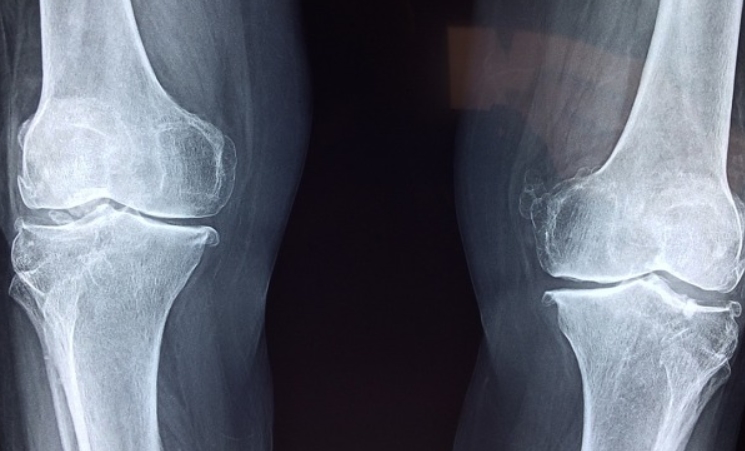

연골이 마모되면 뼈끼리 부딪히면서 통증이 생기는데, 콘드로이친은 그 충격을 줄여주는 역할을 합니다. 관절액의 생성을 촉진해서 움직일 때 더 편안하게 느끼도록 도와주죠. 실제로 부모님께 2~3개월 정도 꾸준히 드렸더니, 무릎 꺾이는 소리도 줄고 아침에 일어날 때 더 수월해졌다고 하시더라고요.

첫째, 연골을 재생시키고 손상을 줄이는 데 도움이 됩니다. 나이가 들수록 마모되는 연골은 스스로 회복되기 어려운데, 콘드로이친은 새로운 연골 세포의 생성을 도와 퇴행성 변화에 제동을 걸어줍니다.

둘째, 관절 사이를 부드럽게 만들어줘서 움직임이 편안해지죠. 관절액 생성을 도와주는 작용 덕분에 마찰이 줄어들고, 아침에 일어날 때 관절이 뻣뻣한 느낌도 덜하게 됩니다.

셋째, 관절염 같은 염증성 질환의 진행 속도를 늦춰줍니다. 만성염증은 관절 기능을 악화시키는 주범인데, 콘드로이친은 염증 매개물질의 활동을 조절해 관절을 진정시켜주는 작용이 있어요.